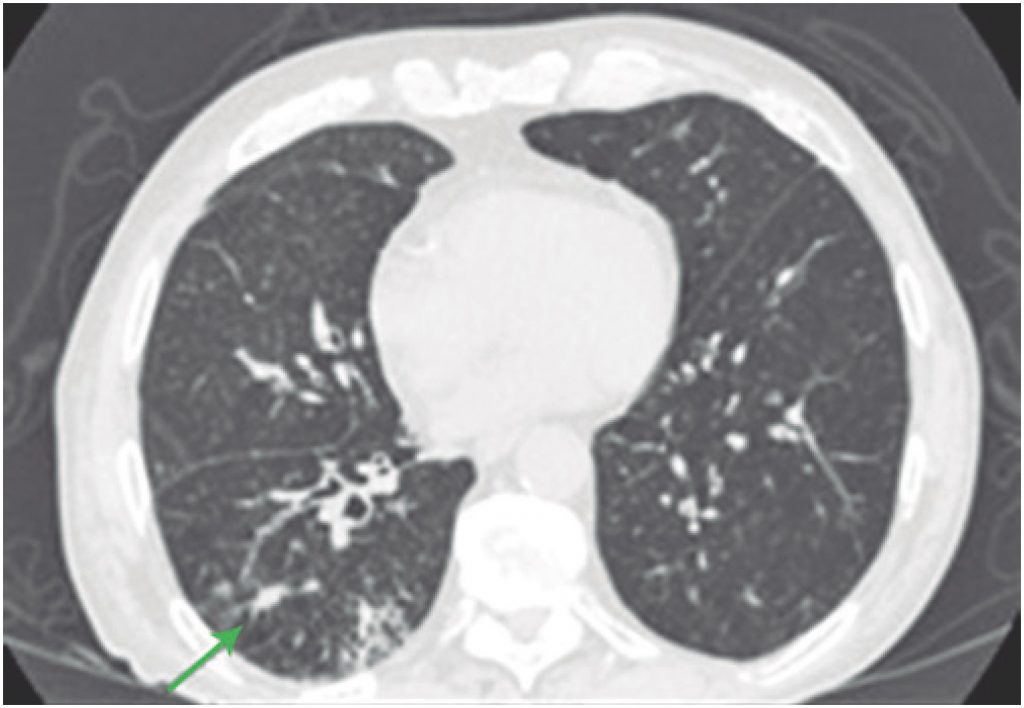

Immunotherapy-induced pneumonitis is a rare complication with incidence estimated around 3%. This disease is difficult to diagnose and has great morbidity. For this reason, it became a challenge for oncologists and emergencists. We reviewed the case of five patients who used anti-PD1 (program cell death receptor antagonist 1) for antineoplastic treatment and developed treatment-induced pneumonitis. All patients had respiratory problems because of immunotherapy and presence of ground-glass radiologic change. Among all patients, only one had grade 5 pneumonitis, and delaying to begin corticosteroid therapy and worsening in clinical picture led to patient death. Other four patients with symptomatic grade 2 pneumonitis underwent corticosteroid therapy and had improvement in clinical and radiologic picture. Two patients were treated after an episode of pneumonitis, and no new pulmonary complications were observed until the end of this study. Immunotherapy-induced pneumonitis, although uncommon, can be potentially fatal. Medical team has the responsibility to pay attention for most common symptoms of the disease such as cough and dyspnea and conduct an early diagnosis and effective early treatment with corticosteroids.